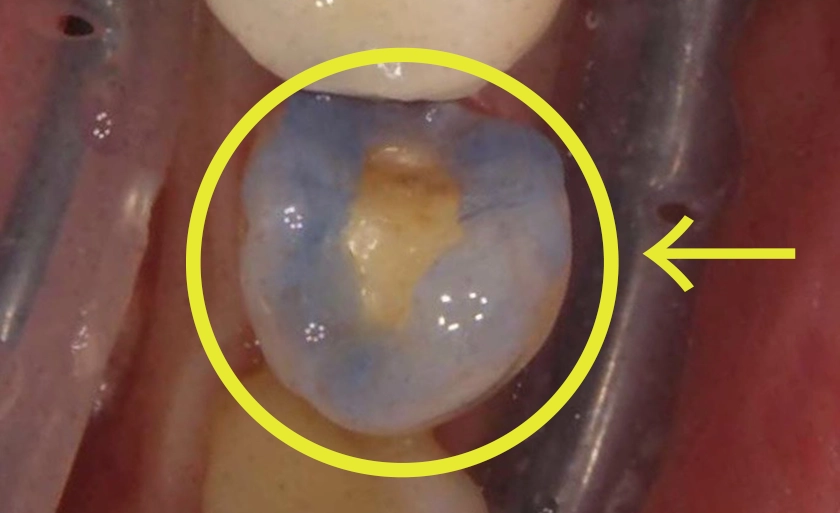

虫歯を削った歯にレジン(複合樹脂)を直接詰める治療法です。保険診療では、15〜30分の限られた時間内で、保険制度で定められた範囲内の基本的な処置のみを行うことになります。

また、十分な診療時間を確保することによる、虫歯治療後の挫滅層などの異物除去、ラバーダム防湿やZOOという異物混入防止器具の使用など、徹底した接着処置が行えます。